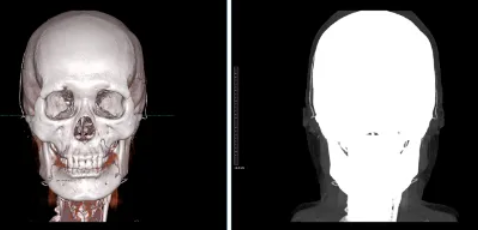

In head and neck imaging, the cerebral blood vessels are located inside the skull, so it is not possible to directly see them by simply taking a CT scan of the contrast-enhanced image. In order to see the cerebral blood vessels, it is necessary to remove the skull, which is called bone subtraction.

Volume rendering results of a CT image taken with contrast agent (left) and the vascular structures hidden by the skull (right)